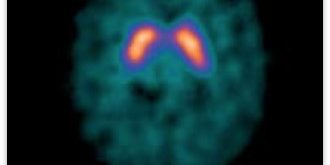

The radioactive tracer binds to the presynaptic dopamine transporters in the brain, in particular the striatal region of the brain. In Parkinson’s disease and Dementia with Lewy Bodies there is a marked reduction in dopaminergic neurons in the striatal region. The tracer binds to the dopamine transporters and gives a semi-quantitative measure and spatial distribution of the transporters.

The scan itself is a single photon emission computed tomography (SPECT) scan of the brain. The patient lies down on the examination couch with their head positioned in the headrest. Often a gentle head restraint is used to minimise motion. The gamma camera rotates around the patient’s head for approximately 30-45 minutes. During this time, it is important that the patient lies still as a three-dimensional image of the distribution of the dopamine receptors in the brain is being created.

The scan needs to be reported by a specialist radiologist who has experience in dopamine transporter studies. Often quantification of the tracer uptake in the basal ganglia can be helpful. There are several software manufacturers which provide a database of normal scans, which the patient’s study is compared against in order to determine whether the scan is abnormal or not. This quantification and comparison with a validated normal database can be very helpful in difficult cases.